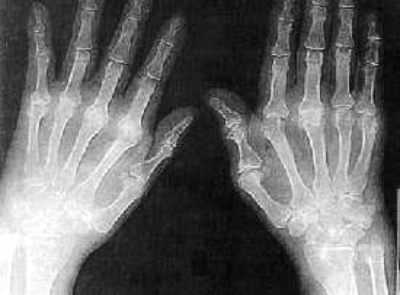

Paciente de sexo femenino de profesión costurera, aproximadamente de unos 40 años acusa dolor en sus manos y articulaciones. Se presenta radiografía de manos. ¿Cuál es su diagnóstico?

Answer

• Manos sanas, se recomienda reposo de las manos, evitando trabajos intensivos, aplicar hielo.

• Osteoporosis, caracterizada por una disminución de la densidad del tejido óseo, causando fragilidad exagerada de los huesos.

• Artropatía  que ataca tanto al cartílago como al tejido sinovial (por donde circula el líquido sinovial), endureciendo el cartílago de las manos.

• Artrítis reumatoide, mostrando en sus características erosiones.